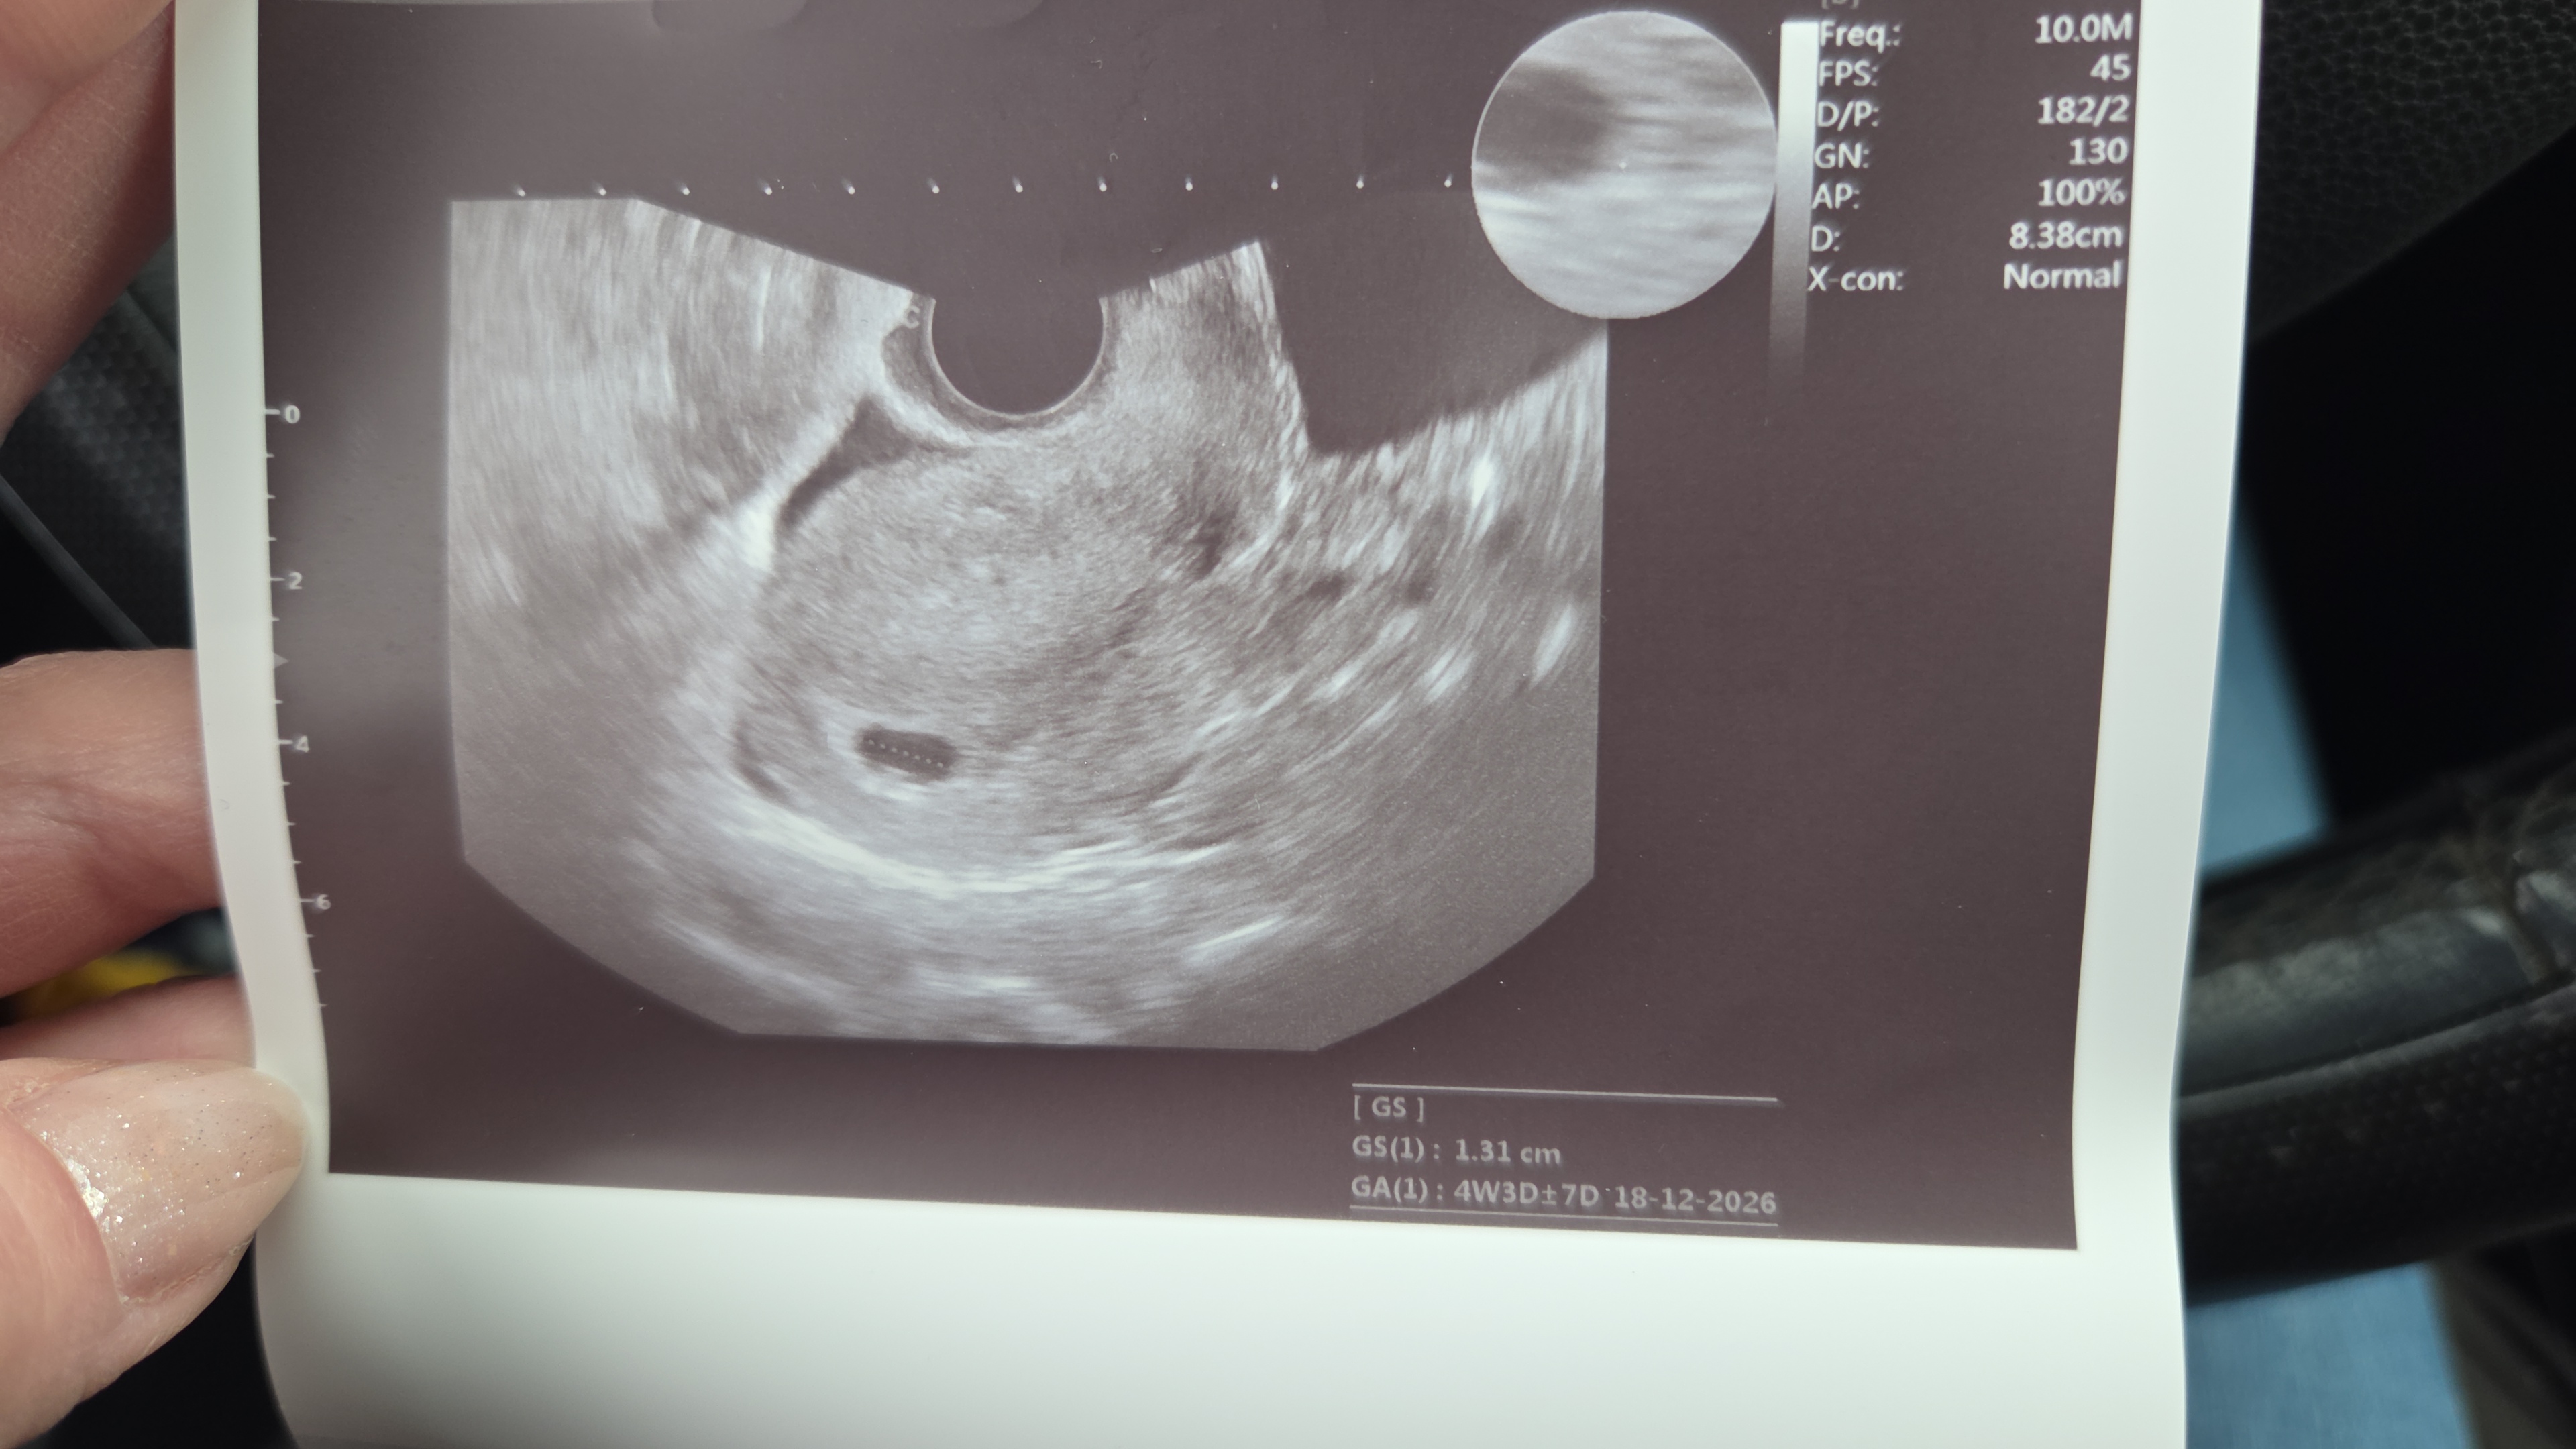

przyszłamama96 wrote:Jeśli mogę zadam to samo pytanie które wyżej skierowałam do Hery, a masz już pęcherzyk żółtkowy i pamiętasz ile mm ma pęcherzyk ciążowy? Ja byłam na USG 4+5 i trochę jestem zestresowana że był sam pęcherzyk ciążowy, zastanawiam się czy nie powinien być też już żółtkowy ale nie zapytałam ze stresu ..

Tak już było widać, u mnie parę dni więcej, bo jakoś 5+3, także nie stresuj się,bo kilka dni i u Ciwbuw będzie, a tydzień dwa będzie serduszko, ja też mogłam się wstrzymać wizyta i pójść na serduszkową, raz ze przy nieregularnych cyklach ciężko to oszacować, owu była później, a dwa chciałam dla spokoju, bo praktycznie zero objawów, gdzie z chłopakami juz wiedziałam "przed testem" i szybko się zaczęło, były objawy i bylam jakoś spokojniejsza, a teraz nawet piersi mnie nie bolą

https://zapodaj.net/plik-MG2HPK41Vf